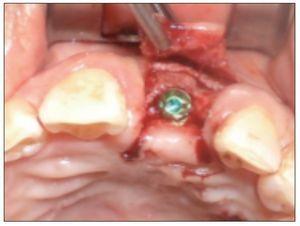

Figura 13. Instalación del implante en zona de pieza 9.

El implante (Superline, Dentium o Tapered Screw-Vent, Zimmer) fue instalado a los 6 meses de realizado el procedimiento de aumento tisular, previa realización de una tomografía computarizada para controlar la ganancia ósea. En 4 pacientes se realizó una técnica sin colgajo, y en los 4 casos restantes se realizó un colgajo mínimamente invasivo.

En todos los casos se realizó una provisionalización inmediata del implante y la restauración definitiva fue realizada a los 4-6 meses de instalado el implante.

Al evaluar los tejidos en el momento de la instalación del implante, se pudo constatar que se logró un grosor de tejido duro ≥ 2 mm por vestibular de cada implante en el momento de su instalación, y a la vez se logró un adecuado grosor de tejido blando > 2 mm en relación con todos los implantes.